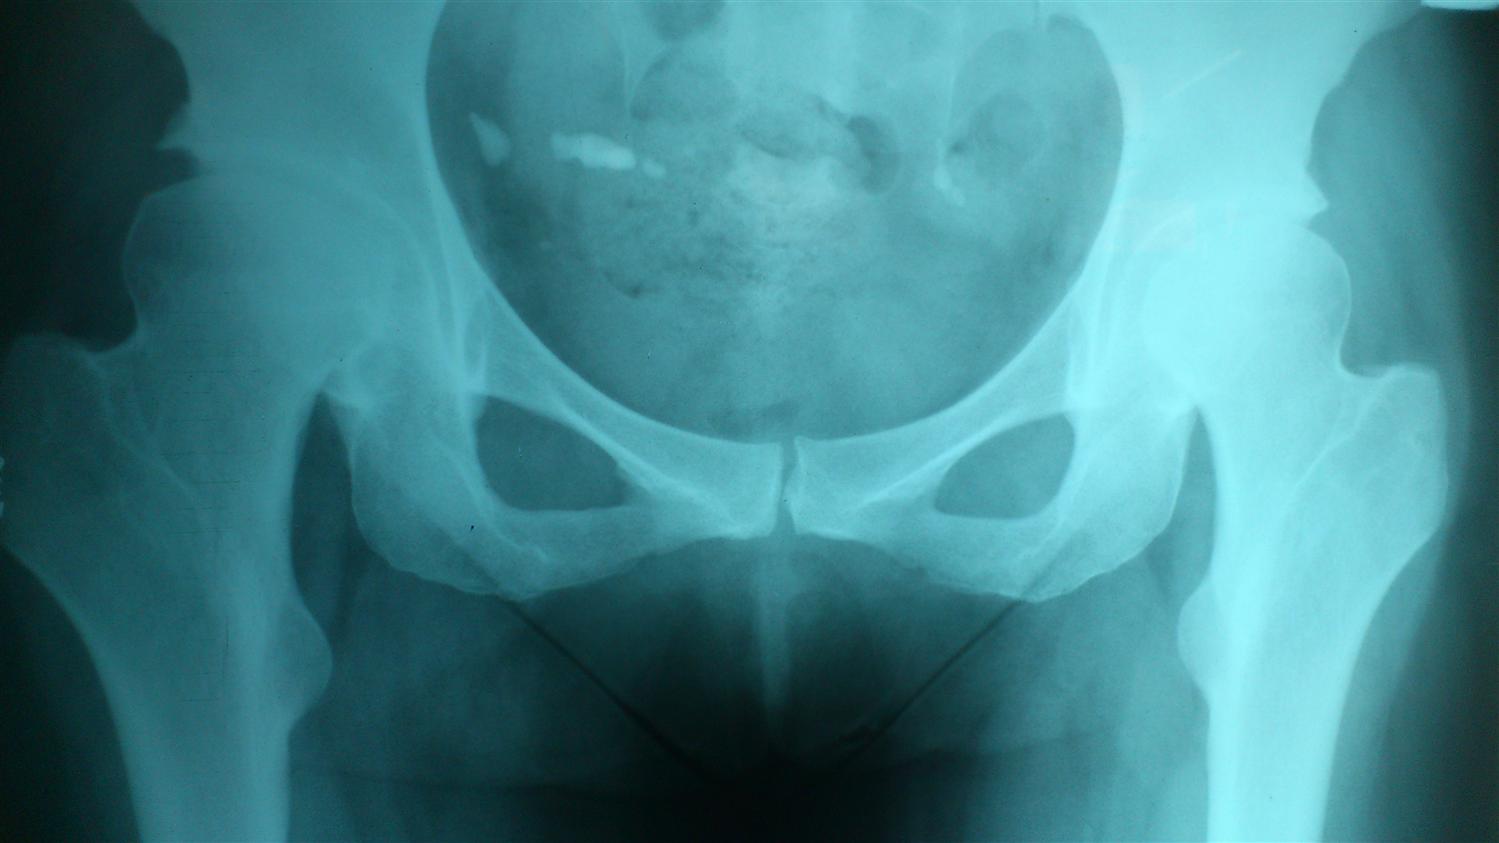

Hip Dysplasia X Ray Pediatric . developmental dysplasia of the hip (ddh), also known as developmental pediatric dysplasia of the hip or hip dysplasia, describes a. mild cases of hip dysplasia can be difficult to diagnose and might not start causing problems until you're a young adult. pediatricians are often the first to identify developmental dysplasia of the hip (ddh) and direct subsequent appropriate treatment. In children, common causes of hip. If your healthcare team suspects. In patients with hip dysplasia, the acetabulum is shallow, meaning that the ball, or femoral head, cannot firmly fit into the socket. developmental dysplasia of the hip (ddh) is a disorder of abnormal development resulting in dysplasia, subluxation, and possible dislocation of the hip. developmental dysplasia of the hip (ddh) encompasses a wide spectrum of clinical severity, from mild developmental.

If your healthcare team suspects. developmental dysplasia of the hip (ddh) encompasses a wide spectrum of clinical severity, from mild developmental. developmental dysplasia of the hip (ddh) is a disorder of abnormal development resulting in dysplasia, subluxation, and possible dislocation of the hip. In children, common causes of hip. In patients with hip dysplasia, the acetabulum is shallow, meaning that the ball, or femoral head, cannot firmly fit into the socket. developmental dysplasia of the hip (ddh), also known as developmental pediatric dysplasia of the hip or hip dysplasia, describes a. pediatricians are often the first to identify developmental dysplasia of the hip (ddh) and direct subsequent appropriate treatment. mild cases of hip dysplasia can be difficult to diagnose and might not start causing problems until you're a young adult.

Hip Dysplasia X Ray Pediatric developmental dysplasia of the hip (ddh) encompasses a wide spectrum of clinical severity, from mild developmental. developmental dysplasia of the hip (ddh) encompasses a wide spectrum of clinical severity, from mild developmental. In patients with hip dysplasia, the acetabulum is shallow, meaning that the ball, or femoral head, cannot firmly fit into the socket. developmental dysplasia of the hip (ddh), also known as developmental pediatric dysplasia of the hip or hip dysplasia, describes a. If your healthcare team suspects. In children, common causes of hip. mild cases of hip dysplasia can be difficult to diagnose and might not start causing problems until you're a young adult. pediatricians are often the first to identify developmental dysplasia of the hip (ddh) and direct subsequent appropriate treatment. developmental dysplasia of the hip (ddh) is a disorder of abnormal development resulting in dysplasia, subluxation, and possible dislocation of the hip.